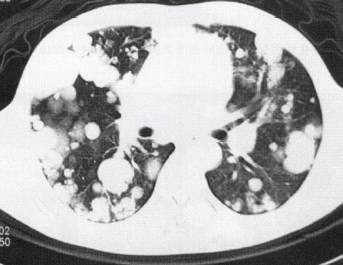

(2)肺转移瘤结节边缘光整,部分病灶融合,出现分叶征。常难与肺癌鉴别,其转移 瘤可能性与原发肿瘤组织类型和患者年龄密切相关,常见原发肿瘤包括黑色素瘤、肉瘤、结肠癌、乳腺癌、肝癌、肾癌、膀胱癌和睾丸癌等(图3)。诊断主要依靠原发恶性肿瘤病史。 医学百科网 | YxBaike.Com